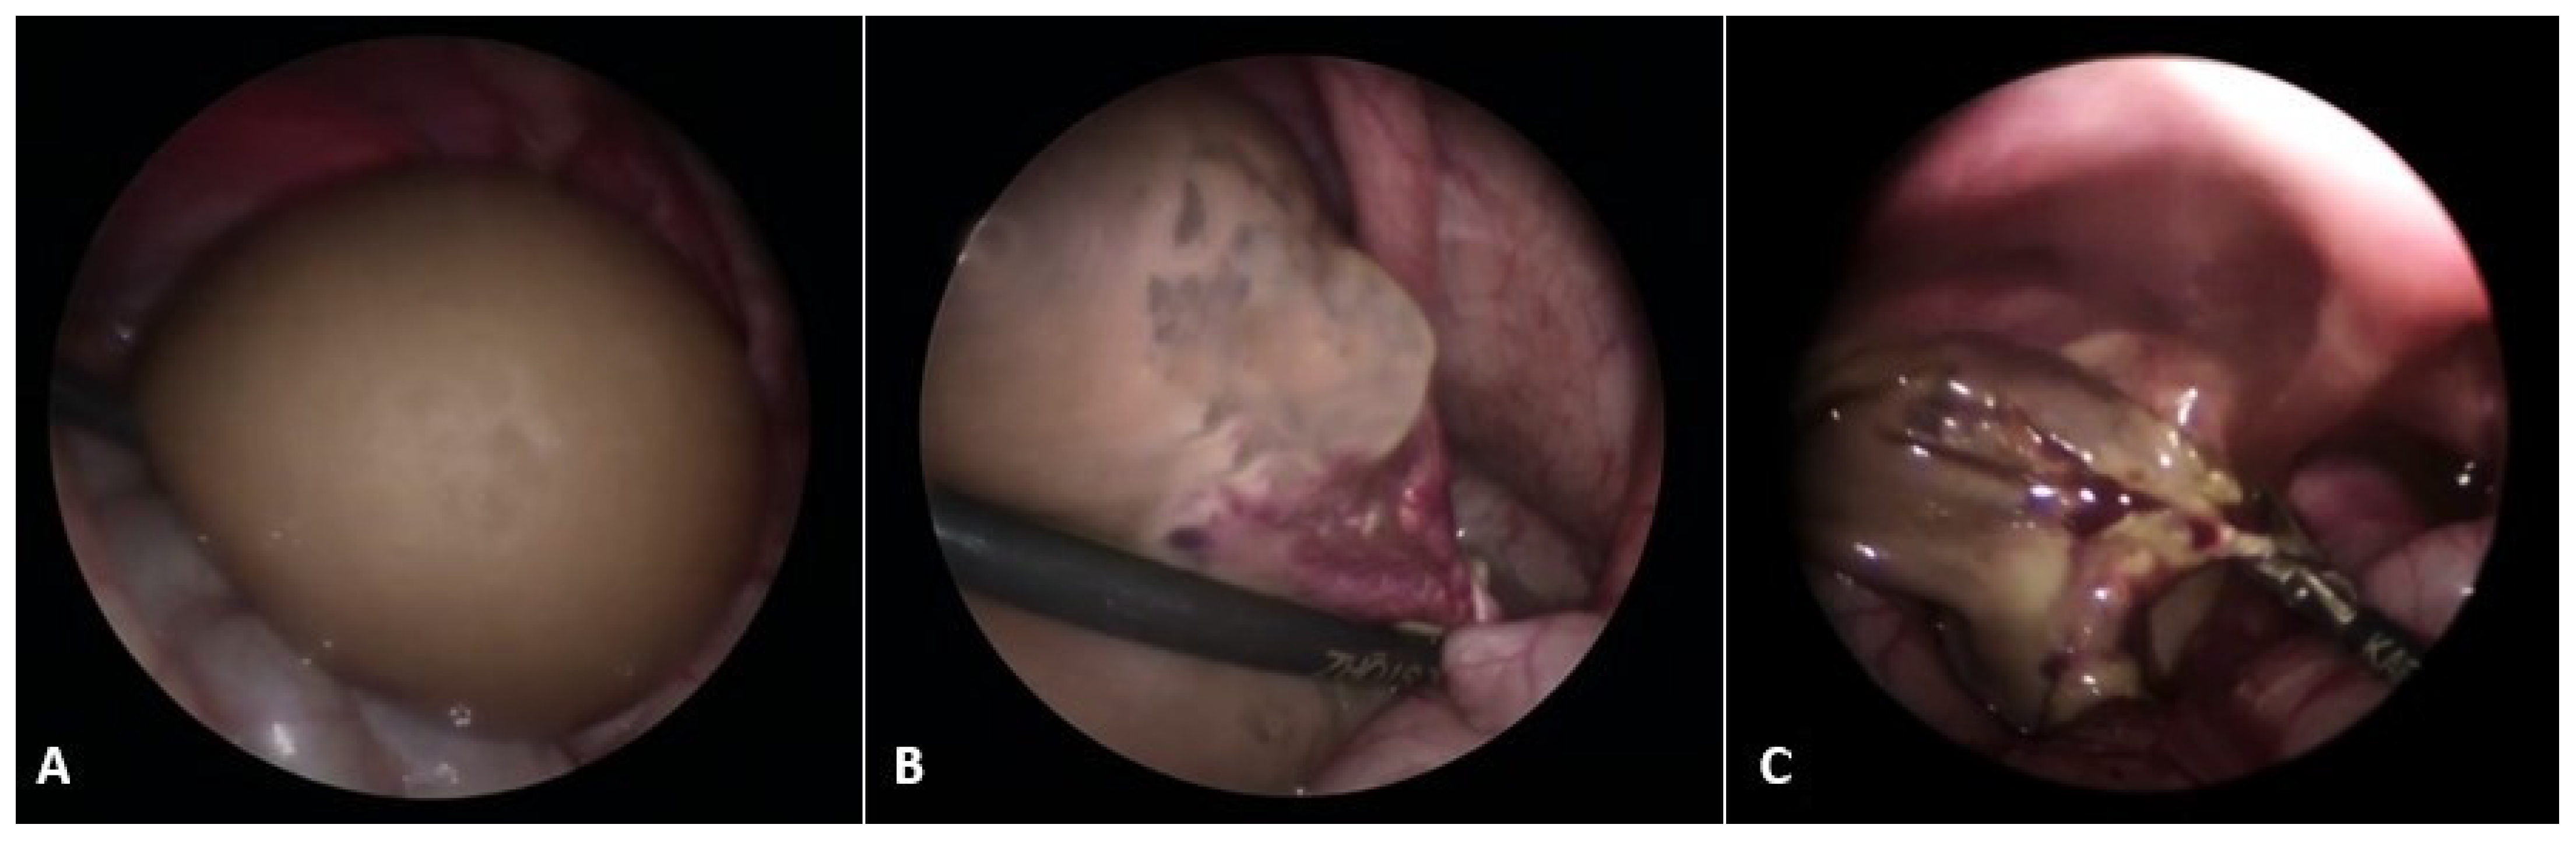

In the phase of adolescence, the possibility of obstructive genital anomalies, ovarian tumors, tubal conditions, uterine masses, and urologic and gastrointestinal conditions should be considered in the differential diagnosis. Ultrasound is the initial imaging modality in differentiating ovarian cysts from other possible conditions [2,47]. As for follicular cysts in adolescent girls, they usually disappear spontaneously within eight weeks. At this age, monophasic combination estrogen/progestin oral contraceptive pills (OCPs) containing ≥35 mcg ethinyl estradiol are commonly recommended, as they inhibit the ovarian-hypothalamic axis and can stop ovulation and the development of a new functional cyst [48,49]. Indications for laparoscopic cystectomy or aspiration are persistence for ≥3 months, size ≥ 6 cm (simple cysts measuring 6 to 12 cm may resolve spontaneously and can be monitored safely in certain patients), pelvic pain, or urinary frequency. Because of the high recurrence rate in the case of aspiration, laparoscopic cystectomy is usually preferred [50,51,52]. For corpus luteum cysts, observation for three months is also recommended for asymptomatic patients. Monophasic combination estrogen/progestin OCPs with ≥35 mcg ethinyl estradiol are also prescribed. Cystectomy alone is rarely warranted. Persistent or non-involuting ovarian cysts should be treated through cystectomy and ovarian tissue preservation (Figure 3) [49,53,54].

Figure 3.

A 14-year-old girl presented with intermittent abdominal pain, loss of appetite, and a palpable abdominal mass. (A) Multislice computed tomography revealed a giant right abdominal ovarian cyst measuring 16.2 × 14.6 cm; (B) The cystic mass filled the entire lower abdomen and was pressing on the surrounding structures; (C) Laparoscopic examination revealed a giant ovarian cyst; (D) The ovarian cortex was opened, 2 L of clear contents were aspirated; (E) A laparoscopic cystectomy with ovarian sparing was performed. A pathohistological examination revealed a simple ovarian cyst. Source: Archive of the Department of Pediatric Surgery, University Hospital of Split.